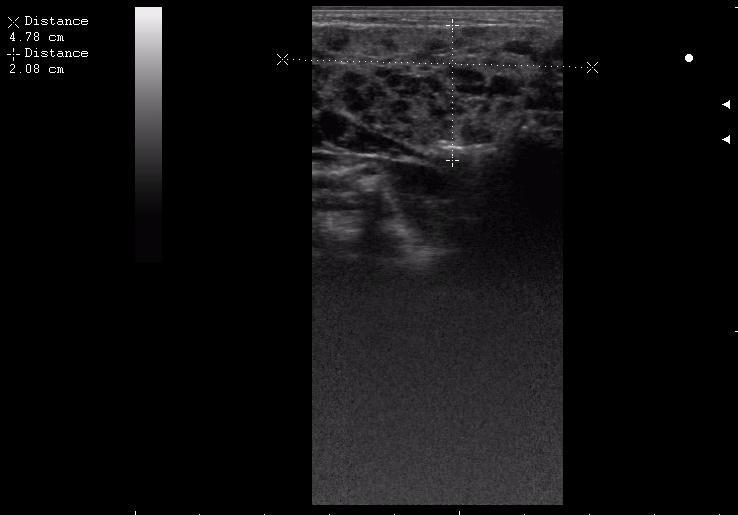

поднижнечелюстная слева